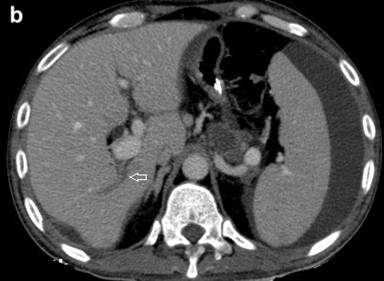

Pancreatitis-associated THAD may arise because of inflammation induced increase in arterial inflow (polymorphous type) [27] or thrombosis in portal, splenic or superior mesenteric veins (sectorial or diffuse type). A sectorial type occurs in the setting of thrombosis of portal vein and typically has a wedge shaped or at least one straight border [23, 27]. When the thrombus is present in the main PV trunk, collaterals in the peri-hilar region maintain perfusion of the central portion. The periphery however, continues to receive undiluted contrast carried by hepatic artery branches with consequent high attenuation of the periphery. Such a pattern is called central-peripheral subtype of diffuse THAD (Figure 4) [27].

|

Figure 4 a. CECT arterial phase demonstrated a sectorial type of transient hepatic attenuation difference with a straight border (solid arrow). Also noted are thrombosis in a tributary of portal vein (arrow) with fluid collection in the body of pancreas. b. CECT venous phase shows near complete resolution of transient hepatic attenuation difference with thrombosis in a tributary of portal vein (arrow). |